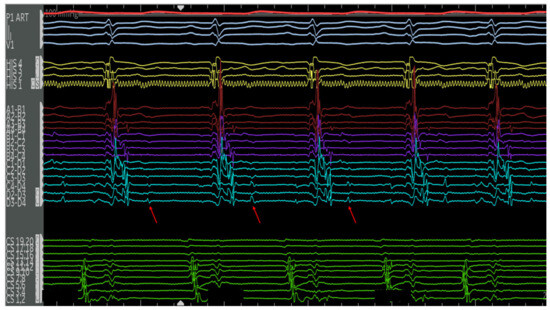

4.2.1. Cases

4.2.2. Case 1

4.2.3. Case 2